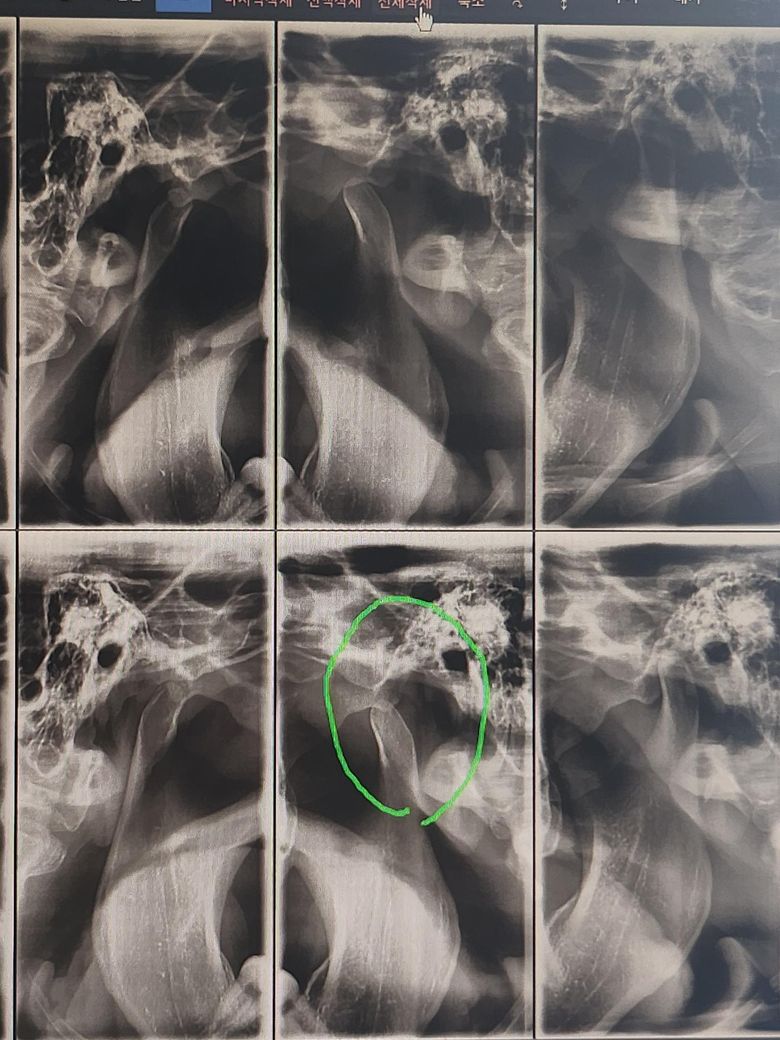

윗줄의 사진은 3년전 사진이고 밑의 줄은 최근 엑스레이 사진입니다.

궁금한 점은 위에줄 엑스레이 사진이 성장이 다 완료된 뼈상태인지?

아니면 3년이 지난 지금 뼈가 더 성장한 것인 지 궁금합니다

질문 주신 사진에서 보이는 차이는 실제 뼈 성장보다는 촬영 각도, 개구 정도, 턱 위치, 자세 차이, 관절 원판 위치 변화, 또는 근육 사용 패턴 변화에 따른 시각적 차이일 가능성이 더 큽니다. 턱관절 X-ray 상에서 보이는 관절두(동그란 뼈)의 크기나 모양 변화만으로 성장 여부를 단정할 수는 없습니다.